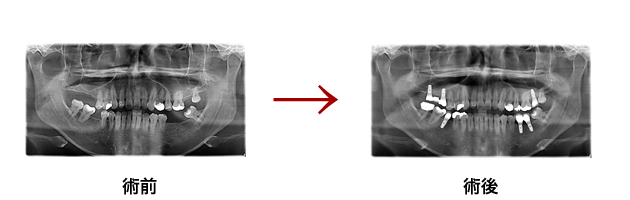

症例集

天然の歯と同様の機能と審美性